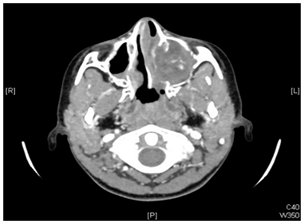

A 9 years old girl, presented with longstanding, left sided nasal obstruction and serosanguinous nasal discharge. She had been experiencing nasal obstruction and intermittent epistaxis for one year already. Her past medical history was otherwise unremarkable. The patient on anterior rhinoscopy, a bulge was detected, arising from the left nasal wall and impinging on the septum. The computed tomography (CT) examination was performed on a spiral scanner. The CT scan obtained following intravenous contrast administration revealed a large, inhomogeneously enhancing mass in the left maxillary sinus and nasal cavity (Figure 1–3). The nasal turbinates and the medial wall of the maxillary sinus had been eroded by the mass. There was also a bony remodeling in the anterior wall of the maxillary sinus. Because of the suspicion of sinonasal cancer, a biopsy was taken to obtain tissue from the nasal cavity and maxillary sinus. However, the biopsy revealed multiple submucosal dilated vessels filled with blood, fibrin deposition and organized thrombi stain for fungal organism negative, findings consistent with hemangioma. The microscopic examination showed dilated sinusoidal vascular channels in the stroma lining with an interconnecting fibrous wall covered with flat endothelium. The Lumina of these spaces were filled with blood. The histologic features were most compatible with cavernous hemangioma (Figure 4). On follow up, patient improvement regarding nasal obstruction and less nasal bleeding.

Figure 2 Axial CT scan showing large, inhomogeneously enhancing mass in the left maxillary sinus and nasal cavity. The nasal turbinates and the medial wall of maxillary sinus had been eroded by the mass.